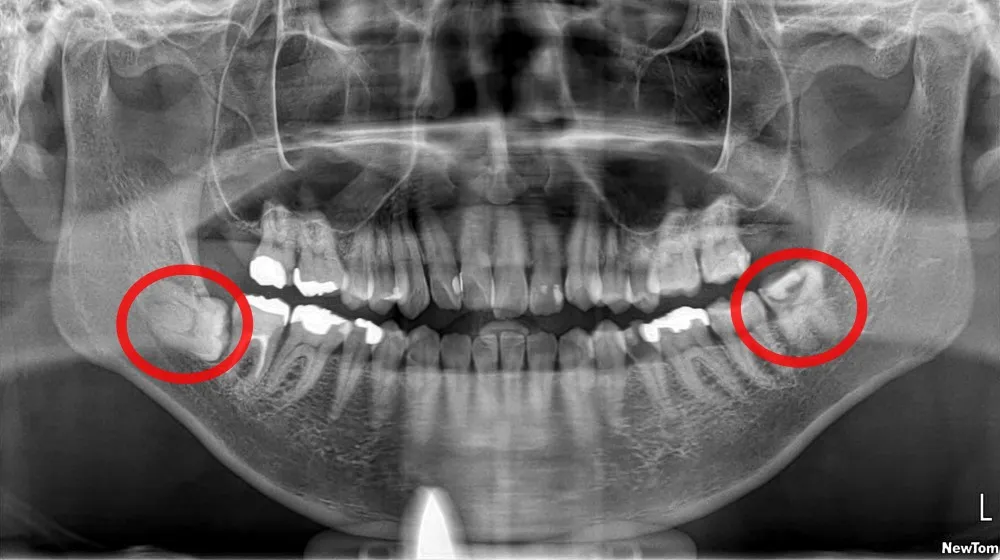

親知らずが骨の中に埋まっていたり(埋伏)、根っこの部分が弯曲・肥大していたりすると、普通抜歯ではなく「埋伏歯抜歯」や「難抜歯」という扱いになり、大学病院などに紹介されることがあります。結心会の口腔外科ドクターたちは、まさにそのような難抜歯症例を大学病院で対応してきたため、難しい抜歯でも対応ができる自信があります。

埋まっている親知らずの抜歯

親知らず抜歯は、親知らずが正常に生えてこない場合(埋没や半埋没)、歯列を圧迫する場合、虫歯や歯周病の原因となる場合、または痛みや腫れがある場合に必要とされます。